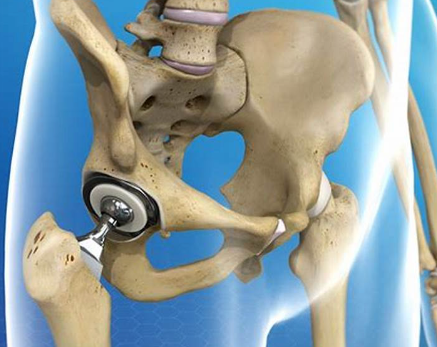

고관절 치환술(Total Hip Arthroplasty)

적응증: 고관절 치환술은 고관절 골관절염, 류마티스 관절염, 무혈성 괴사 또는 고관절 골절이 있는 개인에게 일반적으로 수행됩니다.

절차: 고관절 치환술 중 손상된 고관절의 볼-소켓 구성 요소를 인공 부품으로 교체합니다. 이 절차는 다양한 수술적 접근법을 사용하여 수행될 수 있습니다.

혜택: 고관절 치환술은 통증을 완화하고 고관절 기능을 회복하며 환자가 독립성과 이동성을 회복할 수 있도록 해줍니다.